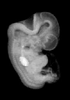

Carnegie Stage 18 (44 post-ovulatory days)

Most embryos at stage 18 are approximately 44 postovulatory days old and measure 13-17 mm in length. Distinguishing criteria for this stage include cervical and lumbar flexures, distinct notching in the hand plate, the first appearance of the elbow, eyelid folds may appear in more advanced specimens, and auricular hillocks begin to form distinct parts of the external ear.